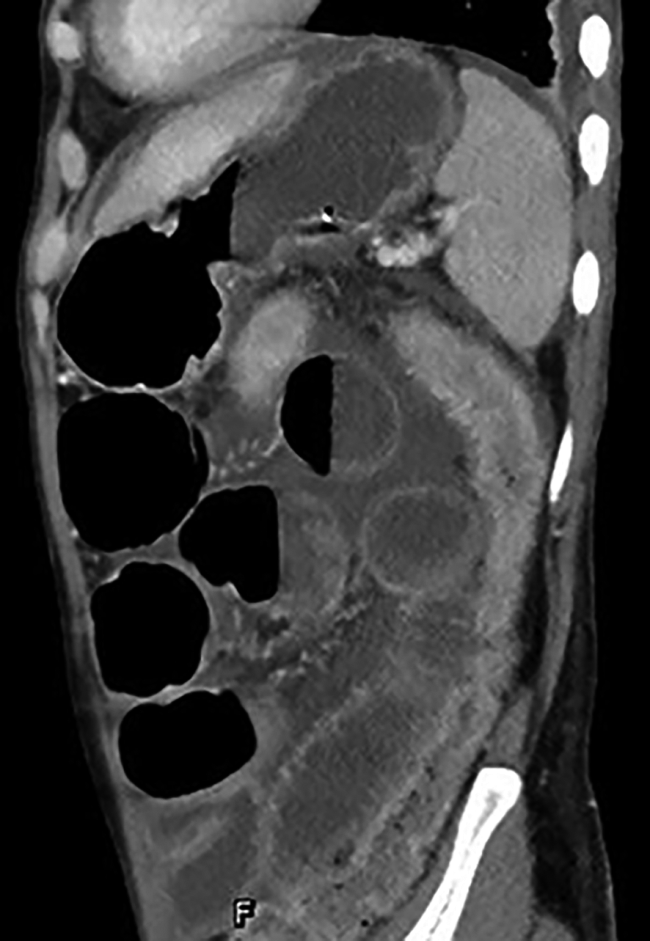

GVHD的发生及演变(图2):HSCT后28 d,患者出现纳差,肝功能总胆红素24.4 μmol/L,碱性磷酸酶355 U/L,谷丙转氨酶116 U/L,考虑急性GVHD肝损害(肝炎型),予调整CsA剂量(图1)联合MP免疫抑制等治疗后病情好转。HSCT后5个月MP、CsA完全停服,6个月患者再次出现纳差、黄疸,总胆红素最高升至57.3 μmol/L,查肝胆彩超未见肝肿大、胆道扩张及梗阻,不支持肝静脉闭塞性疾病,仍考虑急性GVHD肝损害,再次予强化免疫抑制治疗后好转。1年余患者出现口腔溃疡、皮肤疱疹,伴水肿、尿蛋白3+、血白蛋白23 g/L,血肌酐正常,考虑慢性GVHD累及口腔黏膜和皮肤、HSCT后肾病综合征,停用CsA,改为他克莫司,联合MP免疫抑制治疗后症状改善。3年余患者出现全身皮肤呈白癜风样改变,趾甲如病甲改变(图3)。4年余患者水肿、蛋白尿加重,血肌酐升至293 μmol/L,肾活检病理提示GVHD相关的膜性肾病、肾小管间质病变较重(不排除合并慢性肾小管间质性肾炎可能,图4),遂停用他克莫司,改为MMF联合MP免疫抑制治疗。同年血肌酐升至722 μmol/L,进入腹膜透析治疗。9年余患者气促,先后2次胸部CT提示单侧(右)胸腔中-大量积液,胸水检查排除感染及肿瘤,结合患者无右颈内静脉置管病史,无上腔静脉阻塞体征,考虑为GVHD浆膜积液可能,予引流等对症并加用MP治疗后胸腔积液未再复发。此外,HSCT后2年始患者反复出现腹痛、排血性水样便,每次均在予MP免疫抑制治疗后好转,考虑为急性GVHD胃肠道受累。近1年来患者再次发作性血性水样便(图5),胃管引流出血性液体,胃镜(图6)及全腹部CT平扫未见明确占位病变等(图7),不排除胃肠道GVHD症状,经抑酸、护胃等对症治疗后好转。自此截至2022年5月,患者未再使用糖皮质激素及免疫抑制剂,目前处于维持性血液透析、长生存状态。

注:全腹部高分辨CT平扫提示,大小肠管肠壁均见增厚,小肠管内可见积气、积液,肠管扩张、多个气液平面,结肠大部分萎陷,类似不完全性肠梗阻表现